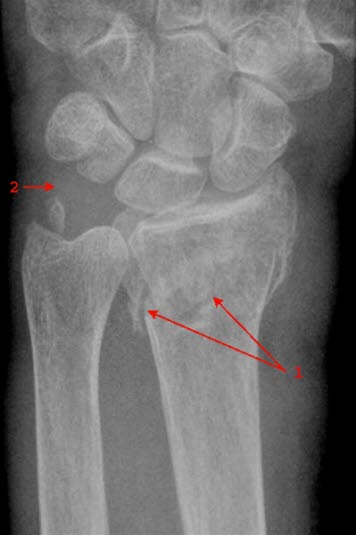

Brudd i nedre del av radius, mindre enn 4 cm fra nedre ende av beinet, betegnes på fagspråket som distalt radiusbrudd eller fractura radii typica. Denne bruddtypen kan medføre at de to bruddendene spriker eller blir forskjøvet i forhold til hverandre, men bruddet kan også være uten forskyvning av bruddendene. I unntakstilfelle kan bruddet skade nerver som ligger nær.

Brudd i håndleddet er den vanligste bruddskaden som forekommer. Bruddtypen er hyppigst hos eldre kvinner, men det er heller ikke uvanlig hos yngre personer. Cirka 90 prosent av bruddene innebærer at det ytterste bruddstykket er skjøvet opp (dorsalt, mot håndryggssiden) - denne bruddtypen kalles også Colles brudd (se tegningen over).

Røntgenbilder tatt forfra og fra siden bekrefter diagnosen (se over). Man ser etter feilstillinger, om det er brudd som innbefatter selve håndleddet, om det er ujevnheter i leddspalten, eller om det foreligger andre beinskader.

Det anbefales operasjon dersom man på røntgenbildene finner tegn til manglende stabilitet i bruddet. Kompliserte brudd som går inn i leddet, eller hvor det er knusning av beinvev, vil alltid bli operert. Den mest brukte operasjonsmetoden er innsetting av en metallplate over bruddspalten. Det er også mulig å stabilisere bruddet med metallpinner som går gjennom huden.